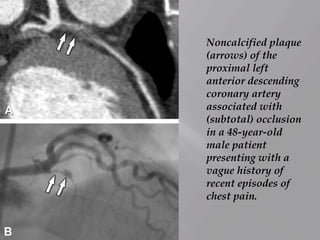

Noncalcified plaque

(arrows) of the

proximal left

anterior descending

coronary artery

associated with

(subtotal) occlusion

in a 48-year-old

male patient

presenting with a

vague history of

recent episodes of

chest pain.